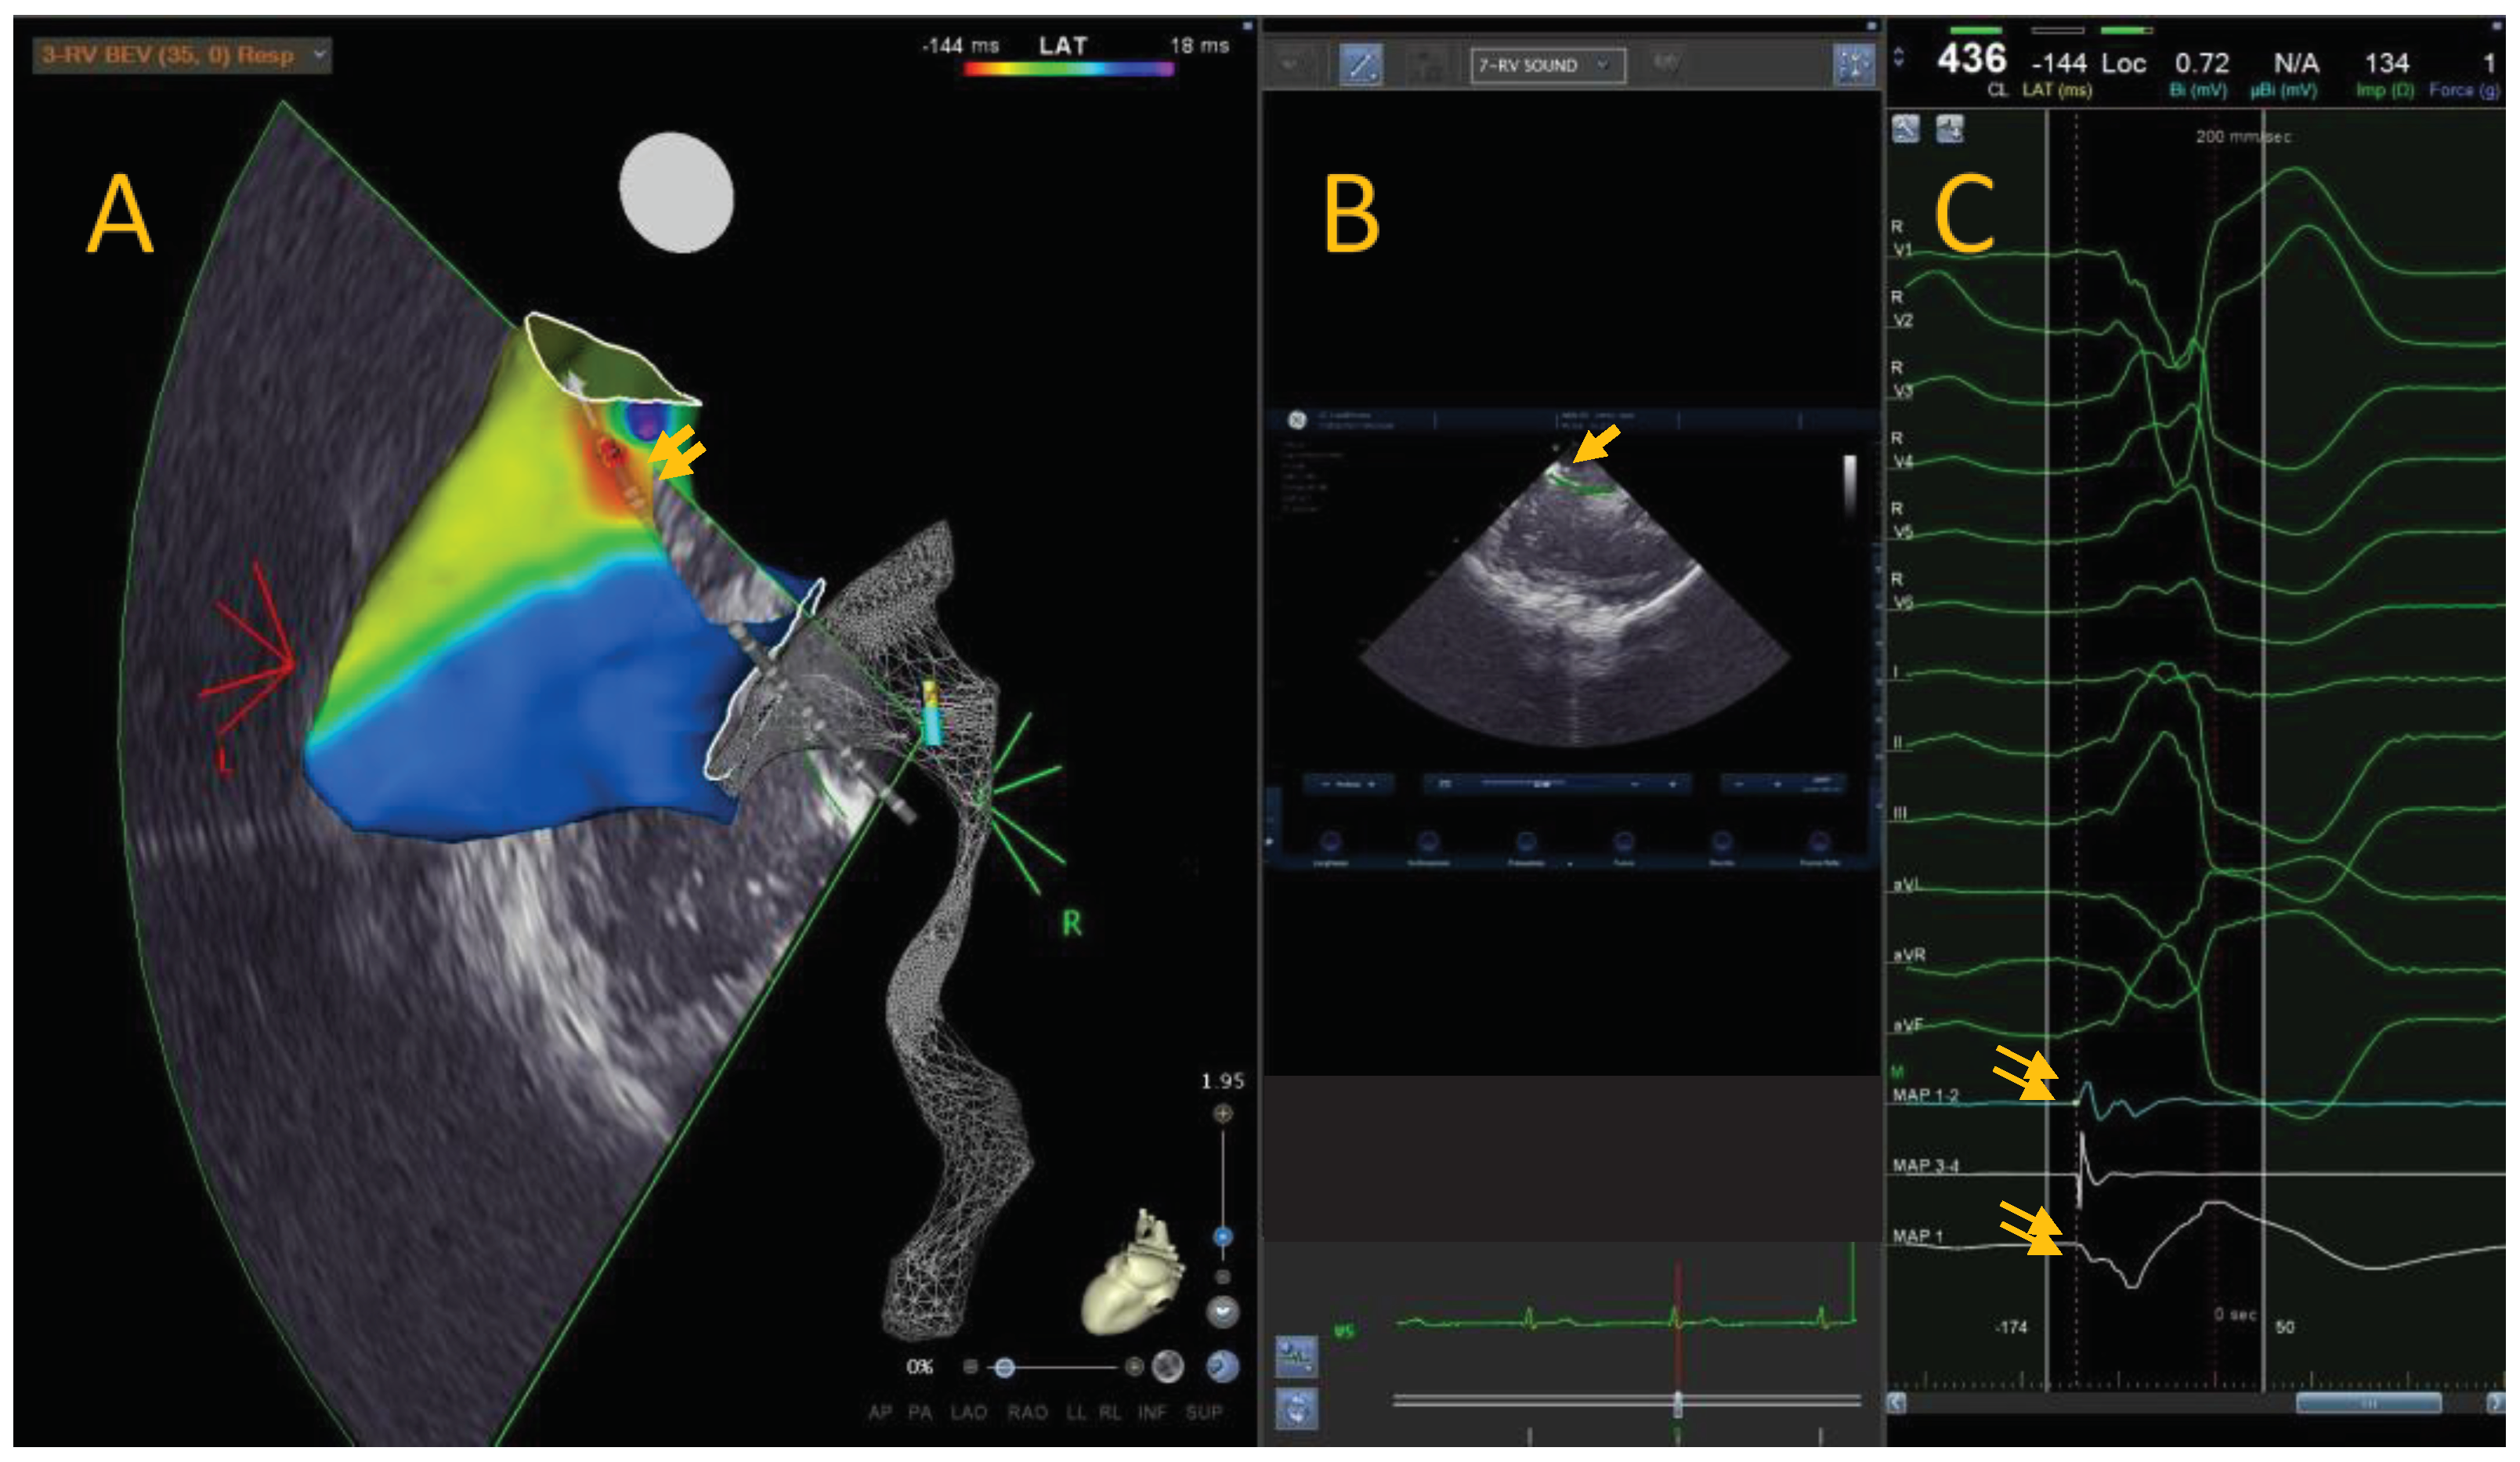

Anatomical mapping data were collected using a 3D mapping system (CARTO 3, Biosense Webster) and a conctact force mapping-ablation catheter (ThermoCool SmartTouch, Biosense Webster Inc., MA, US). The activation mapping was performed in each case: the PVCs origin site was defined as the earliest site of local ventricular activation preceding the onset of the QRS wave by at least 30ms on the surface ECG and with a QS signal in unipolar mapping (Figure A).

Figure A. Local activation time map of a 36-years-old leisure time sportsman with idiopathic PVCs from RVOT. The colorimetric map shows that the main site of onset of PVCs is the posterior RVOT. In this region, we can see the ablator catheter in transparency, with the tip at the level of the region of interest (A). Through intracardiac echocardiography and specific module (CARTOSOUND® Module with SOUNDSTAR®) it is possible to integrate the electro-anatomical map with intracardiac echocardiographic map. It is possible to view the position of the catheter and tip with the ICE (B). The bipolar ablator catheter signal shows a clear advance compared to the surface QRS signal, and the unipolar signal is represented by a QS signal (C).